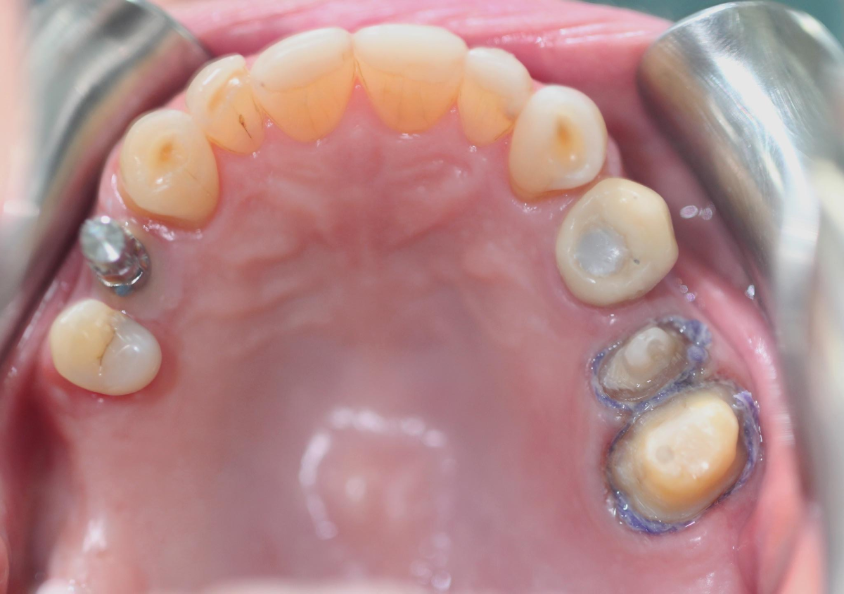

Fixed and Implant-retained prostheses impressions:Restorations on the maxilla

Prepare the teeth (25 and 26). The component (transfer impression) retained on the implant (tooth 14).

Take the impression and get accurate impression results with PERFIT Putty and Light Body.

Note the fluidity of the material in the gingival sulcus after gingival displacement with a retraction cord, achieving an excellent replica of the entire dental perimeter.